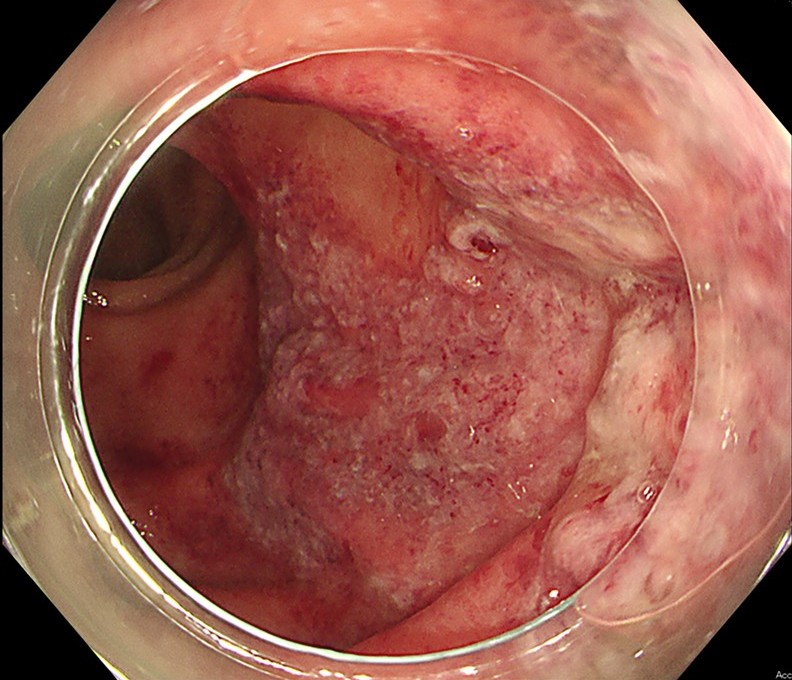

内視鏡検査(大腸カメラ)

大腸カメラが最も重要な診断方法です。

- 腸の粘膜を直接観察し、虚血によるむくみ、赤み、出血、そして特徴的な潰瘍(ただれ)を確認します。

- 典型的な例では、横行結腸からS状結腸にかけて、縦に走るような潰瘍が見られます。

- 潰瘍性大腸炎やクローン病といった炎症性腸疾患など、他の病気と区別するためにも役立ちます。

- ただし、お腹に強い炎症が起きている場合や、腸が壊死している可能性が高い場合は、検査ができないことがあります。